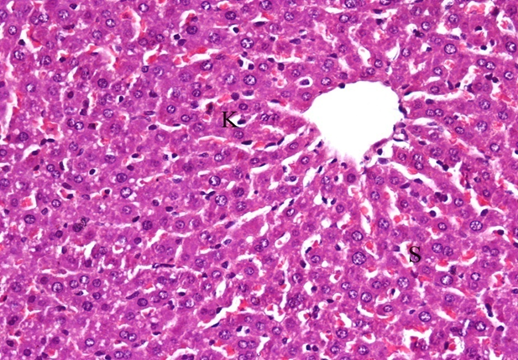

In the group received ginger and carrier showed nearly normal structure with few Kupffer cells and hemorrhage blood sinusoids (fig. 4 and 5).

Fig. 4: It shows photomicrograph of section from liver of Carrier group (H and E X 400)

Fig. 5: It shows photomicrograph of section from liver of ginger group (H and E X 400)

Histopathological examination of group received Sodium salicylate nanodrug showed almost the hepatic structure appear normal except few Kupffer cells and blood sinusoids (fig. 6). Hepatic sections of the rats that protected with Sodium salicylate and cisplatin showed ameliorate effect with inflammatory cells, necrotic cells, and congestion central vein and blood sinusoids (fig. 7).

Fig. 6: It shows photomicrograph of section from liver of Sodium salicylate group (H and E X 400)